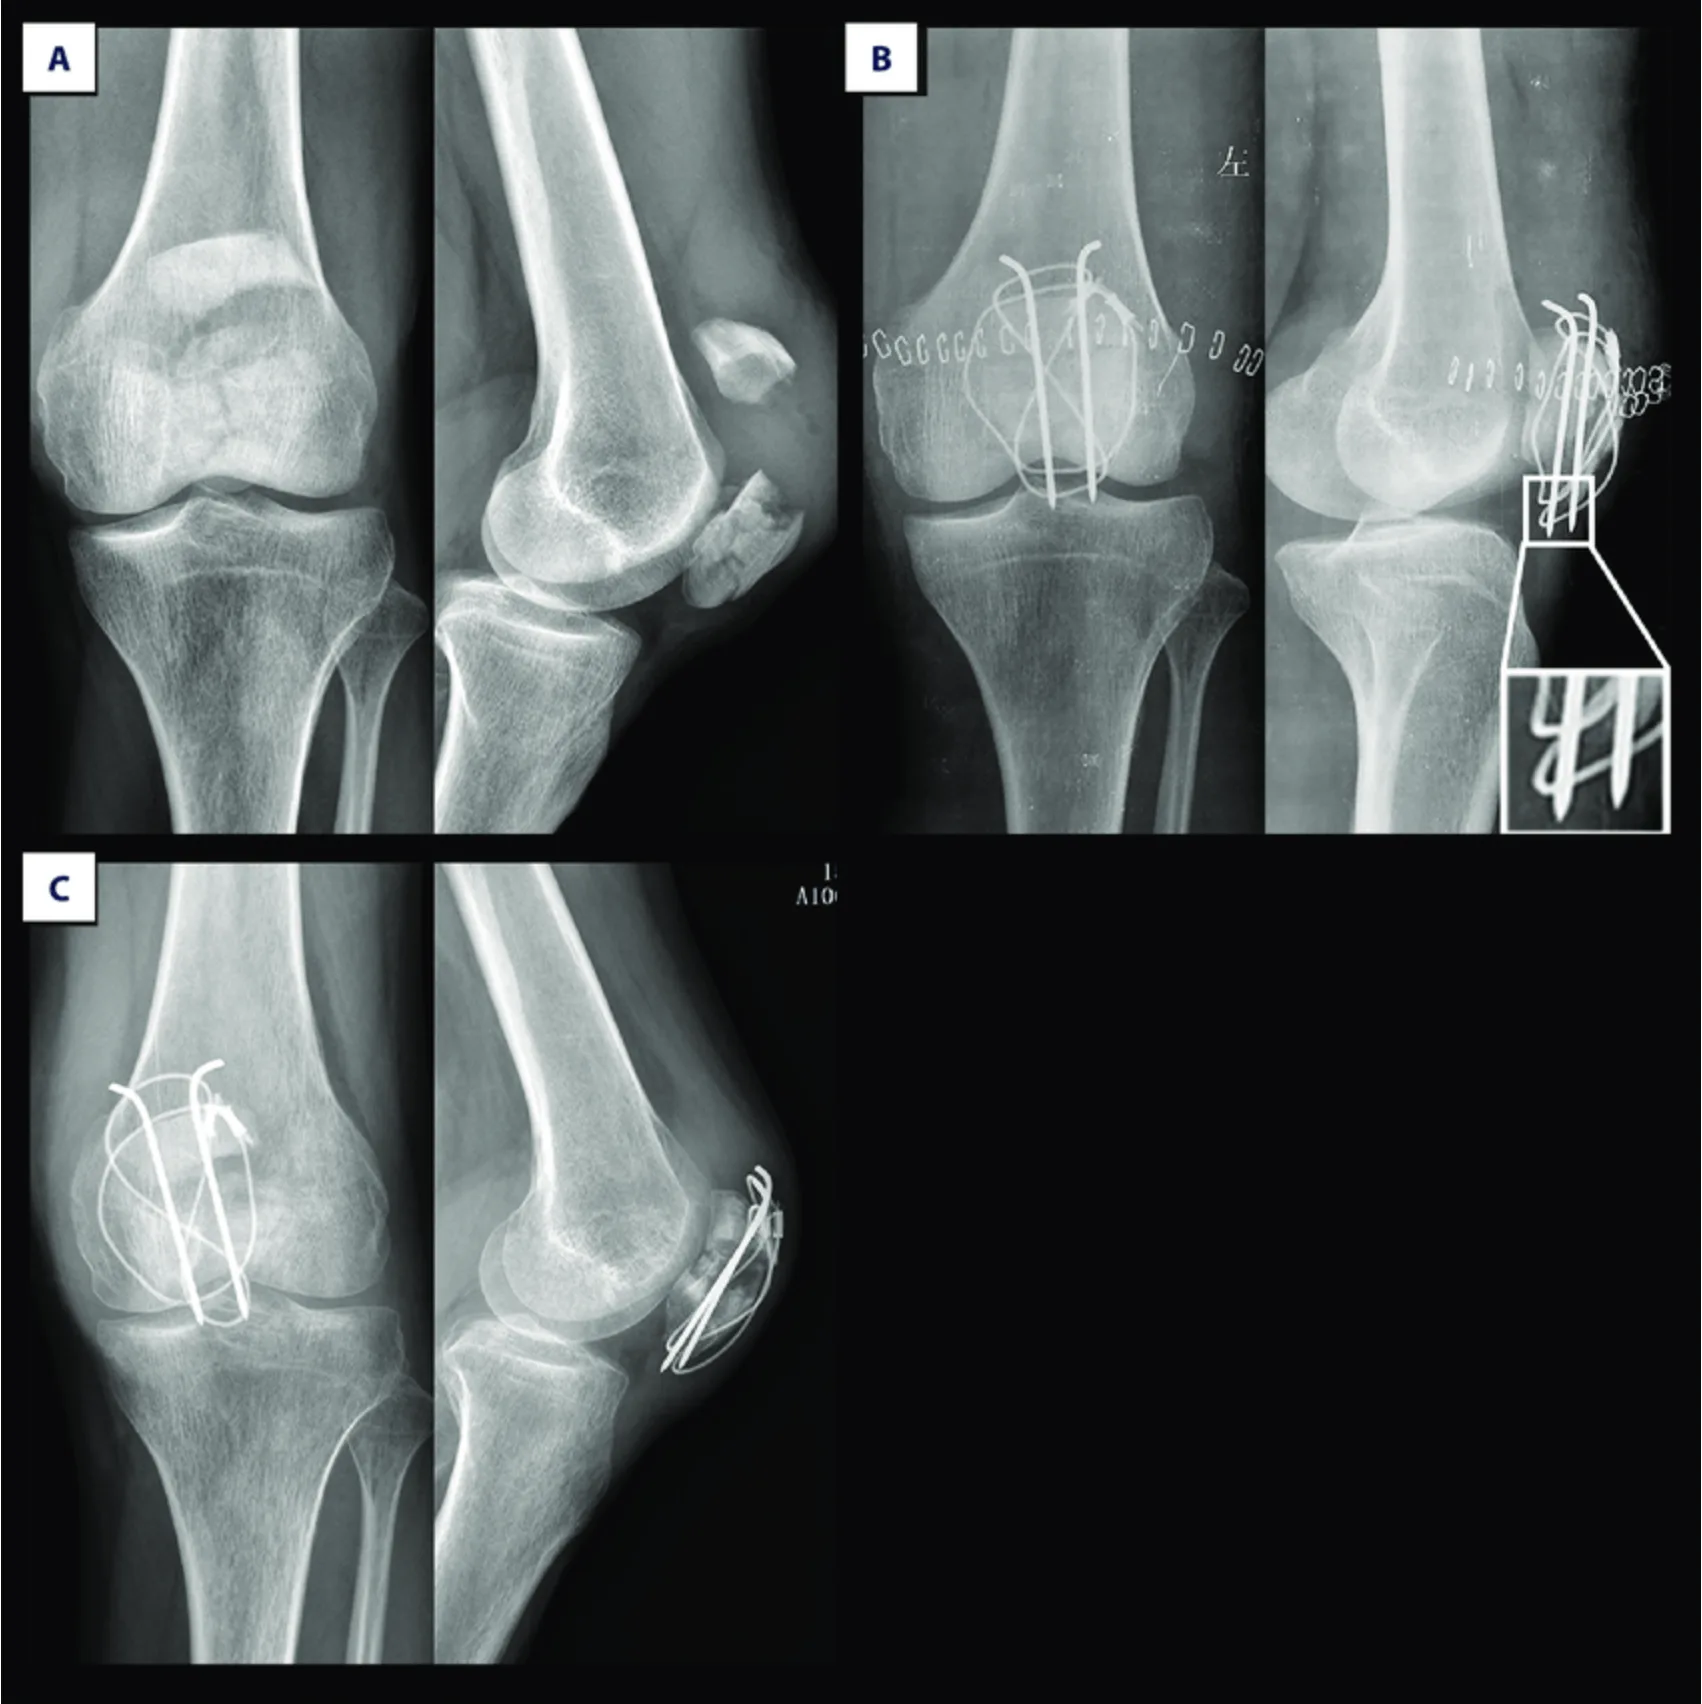

Cでは, 軟鋼線が鋼線のから外れてしまって, 骨折部が開いてしまっています.

続いて14時から, 膝蓋骨骨折の再手術を担当.

1週間前に行ったテンションバンドワイヤリング法による固定後, ワイヤーが緩み骨折部が開大してしまった症例でした.

骨折部が開かないように強力な樹脂製のテープで補強して, 1時間ほどで手術を終了しました.